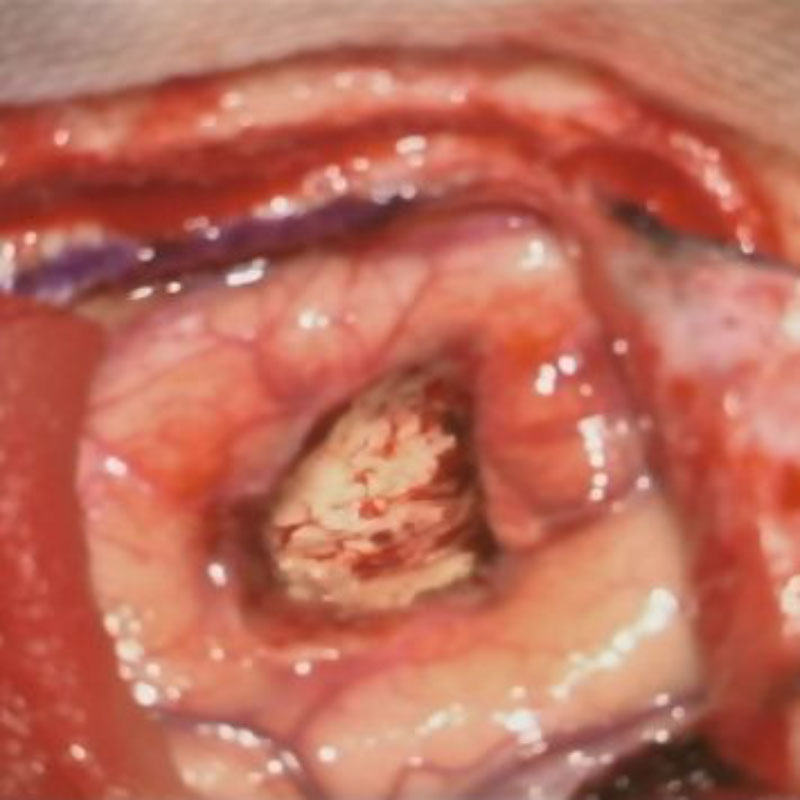

術中写真

摘出 前

摘出 中

摘出 後